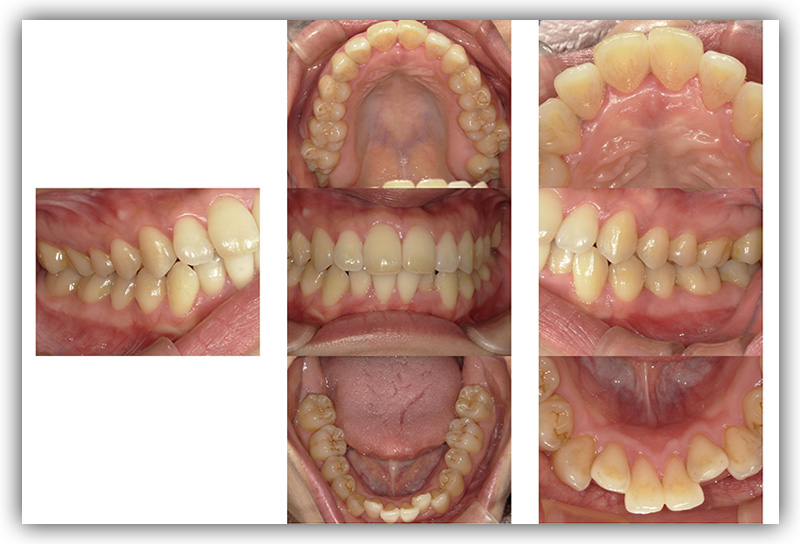

CASE_02

30代女性(インビザライン矯正)

- 患者さん情報(年齢・性別)

- 30代 女性

- 主訴

- 歯並びが気になる。自身の矯正について知りたい。

- 治療箇所

- 1箇所

- 治療方法

- インビザライン

- 費用

- 66万円

- 治療期間

- 1年4か月

- その治療によるリスク・副作用

- 歯肉退縮することがある

- 矯正中はしみたり、痛みを伴うことがある